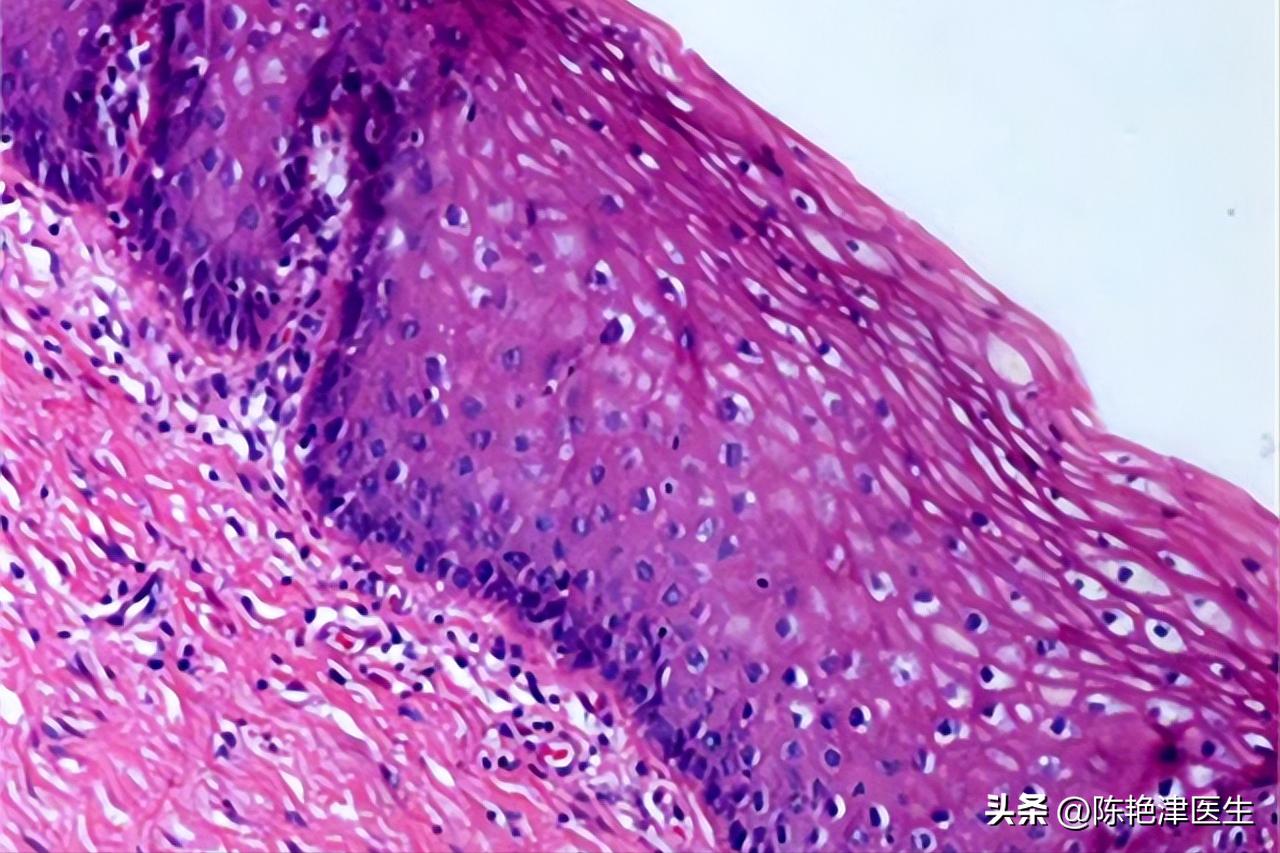

可以通过在相应的部位取组织活检,例如宫颈,观察是否有鳞状细胞的变化。

在组织切片显示的 癌细胞 在病变部位混乱排列形成乳头状、条状等各种形状的结构,并且逐渐向周围或者更深处扩散。